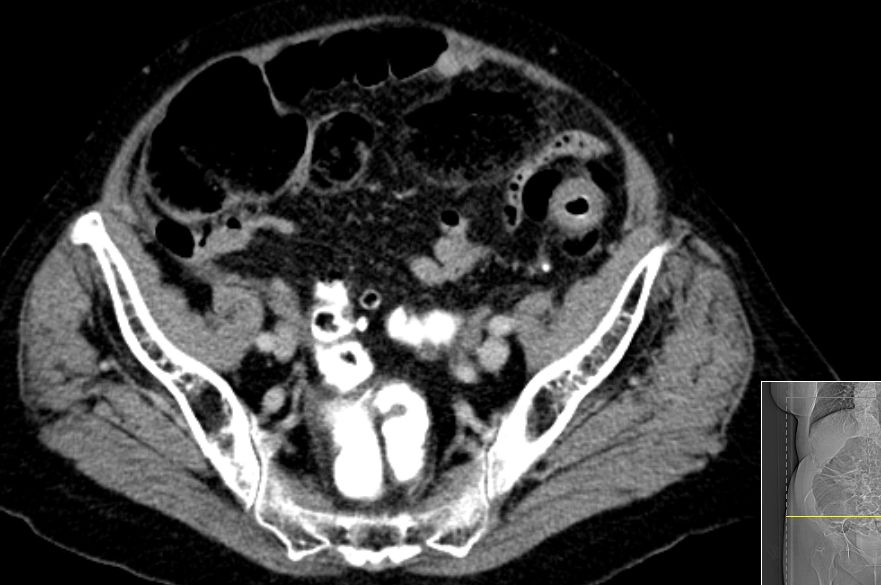

| Klinik | 72jähriger Mann mit kaffeesatzähnlichem, rötlichen Urin und 15kg Gewichtsabnahme. Stuhldurchmesser seit 4 Monaten vermindert.![]() |

| Metastasen | zahlreiche vergrößerte Lymphknoten paraaortal, paracaval und mesenterial.![]() |